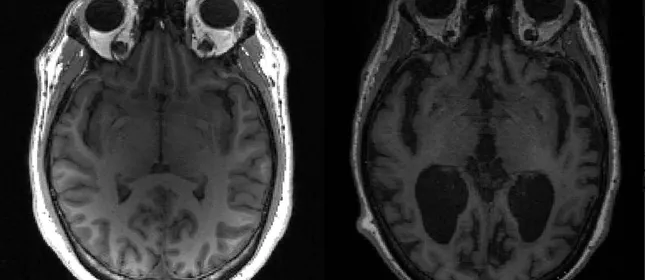

Imagem mostra cérebro saudável à esquerda e cérebro com Alzheimer à direita. Reprodução – Foto: Reprodução

A FDA, agência que regula medicamentos nos Estados Unidos, aprovou nesta terça-feira (2) um novo tratamento para Alzheimer. Trata-se do donanemabe, um medicamento fabricado pela farmacêutica Eli Lilly and Company, indicado para pessoas com sintomas iniciais da doença, o que inclui pacientes com comprometimento cognitivo leve (CCL) e com patologia amiloide confirmada.